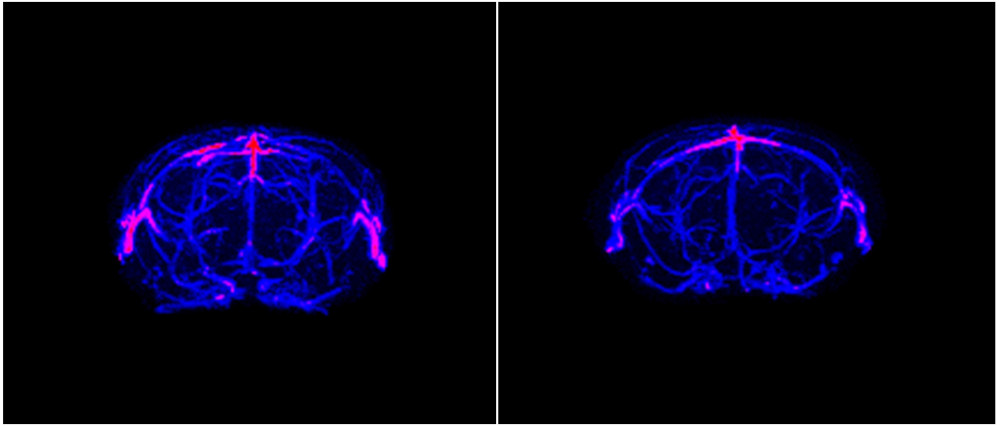

MRI/PET equipment at the IIBM